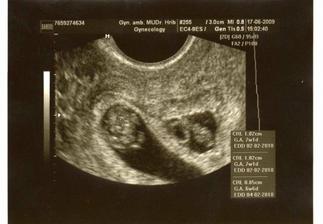

10.6. - první oficiální UTZ v CARu- 2 srdíčka, uvidíme, jak se poperou